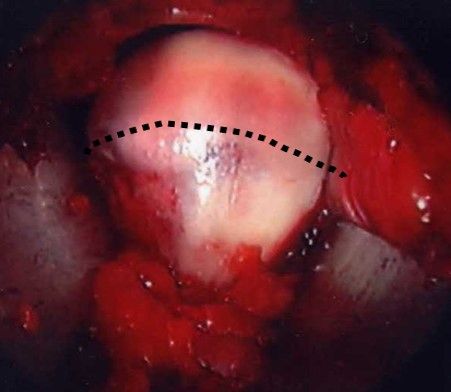

Details of the following steps have been described by (Hartmann and Gunther 2009). By disconnecting the traction device, a dynamic evaluation of hip motion under direct observation of labrum, head and neck is performed and the area of reshaping of the head–neck junction can be clearly defined (fig. 3d).

Visualisation of the central compartment of the joint for chondral and labral lesions is performed arthroscopically. After having applied distraction of the leg a 3.5 mm arthroscope (70° optics) is inserted from the anterior incision. Fluid management as in normal arthroscopy with continuous flow allows proper visualisation. The anterosuperior and lateral parts of the acetabular labrum with the adjacent articular cartilage and the femoral head are inspected. These are the areas where most of the relevant labrum and cartilage lesions are located. Depending on the amount as well as type of damage, reconstructive procedures are performed with and without traction. Ossified or ruptured parts of the labrum are resected or refixation of a partially detached labrum is performed with resorbable suture anchors (fig. 4a and 4b). Refixation of debonded cartilage flaps (fig. 5 a–d) curettage and microfracturing of damaged cartilage fragments and even autologous chondrocyte transplantation is possible (Bretschneider et al. 2020).